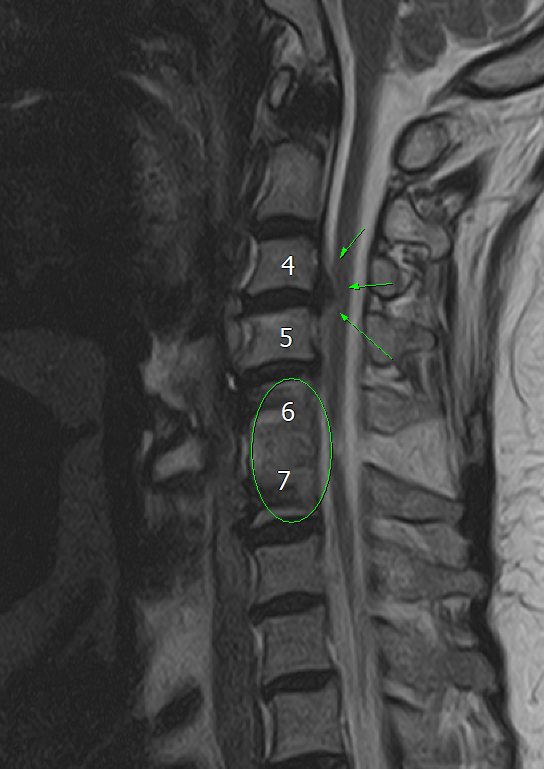

경추 6-7번 사이에 유합술이 되어있다.

그러나, 유합술이 되어있는 상태에서는 해당 유합술 인접부에 문제가 생기는 경우가 흔하다.

Adjacent segement disease (인접분절 질환) 이라고

불리는 것인데,

척추 유합술을 하고 난 이후

원래는 골고루 분산되던 힘이 유합술로 인해 분산이 이루어지지 않으며

위, 아래 쪽의 척추 및 디스크, 신경이 나오는 길 쪽으로 퇴행성 변화 등을 일으키는 것이다.

이로 인해 협착증이나 디스크 증상이 나타날 수 있다.

MRI 검사가 필요하다.

결국 환자분이 느끼는 증상은 목에서 올 가능성이 높고,

X-ray 로는 제한적인 정보밖에 알 수 없기 때문에 MRI 를 찍어야 한다.

예상대로, 6-7번 유합술 된 주변,

C4-5, C5-6, C7-C8 사이로

디스크 탈출 및 퇴행성 변화, 협착 등

인접분절 질환을 보여주는 양상을 확인할 수 있다.